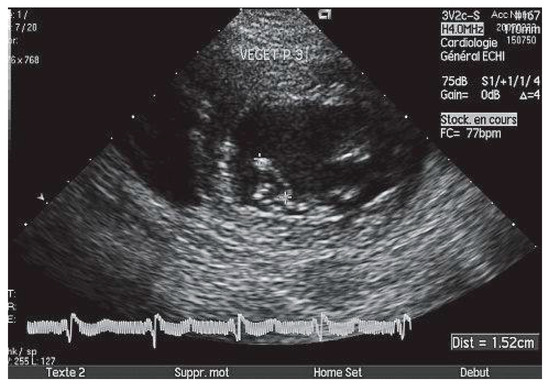

Echocardiographie et Sources Cardiaques d'embolie

• Ariel Cohen

Cardioembolic stroke is the second cause of ischemic stroke, with a high rate of morbidity and mortality. Echocardiography, mainly transesophageal echocardiography, is very useful for the diagnosis and risk stratification of the various potential car...